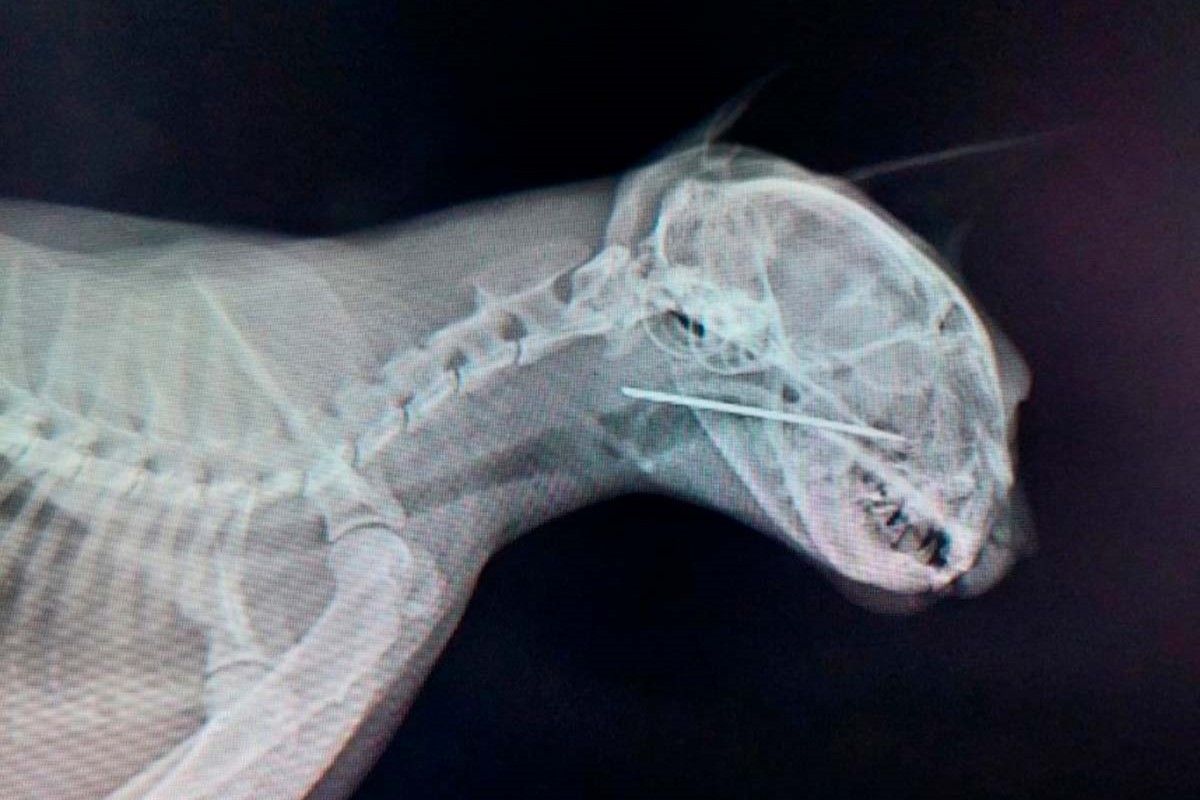

Кот съел человека

Кот съел человека 115 фото